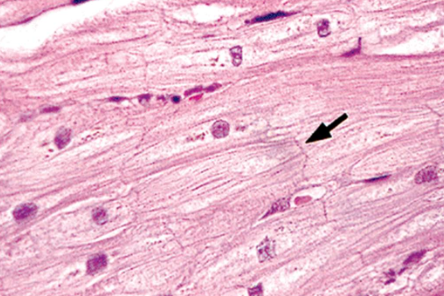

Intercalated disks

arrow